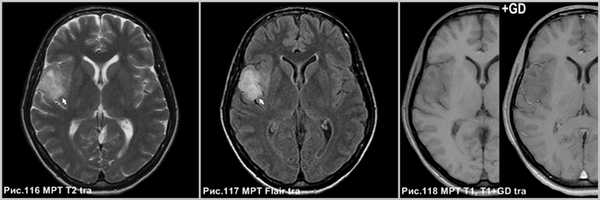

Фибриллярная астроцитома в виде диффузного поражения правой височной доли (стрелки на рис.116-117), не накапливающее контраст (рис.118).